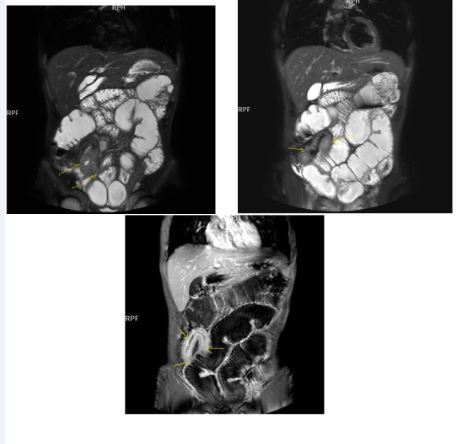

Figure 5a.Enhancing bowel segments due to Crohn’s disease, on T1W post-contrast axial image, luminal enhancement is predominant, shown at 62 years old female with mild disease status.

Figure 5b.İrregular bowel wall and luminal enhancement of ileum, with loss of valvula conniventes on T1W coronal post-contrast sequence, seen on 26 years old male with moderate inflammatory bowel disease.

Figure 6a.Diffuse homogeneous contrast enhancement on the bowel wall and mucosa due to Crohn’s disease, seen at T1W post-contrast axial image, indicated at 23 years old male with mild disease status.

Figure 6b.Heterogeneous bowel wall and mucosa involvement with collaborating skip lesions, specific for Crohn’s disease, predominant in ileum and terminal ileum which are shown at T2W coronal sequence after OCA, regarded at 39 years old female with severe disease.